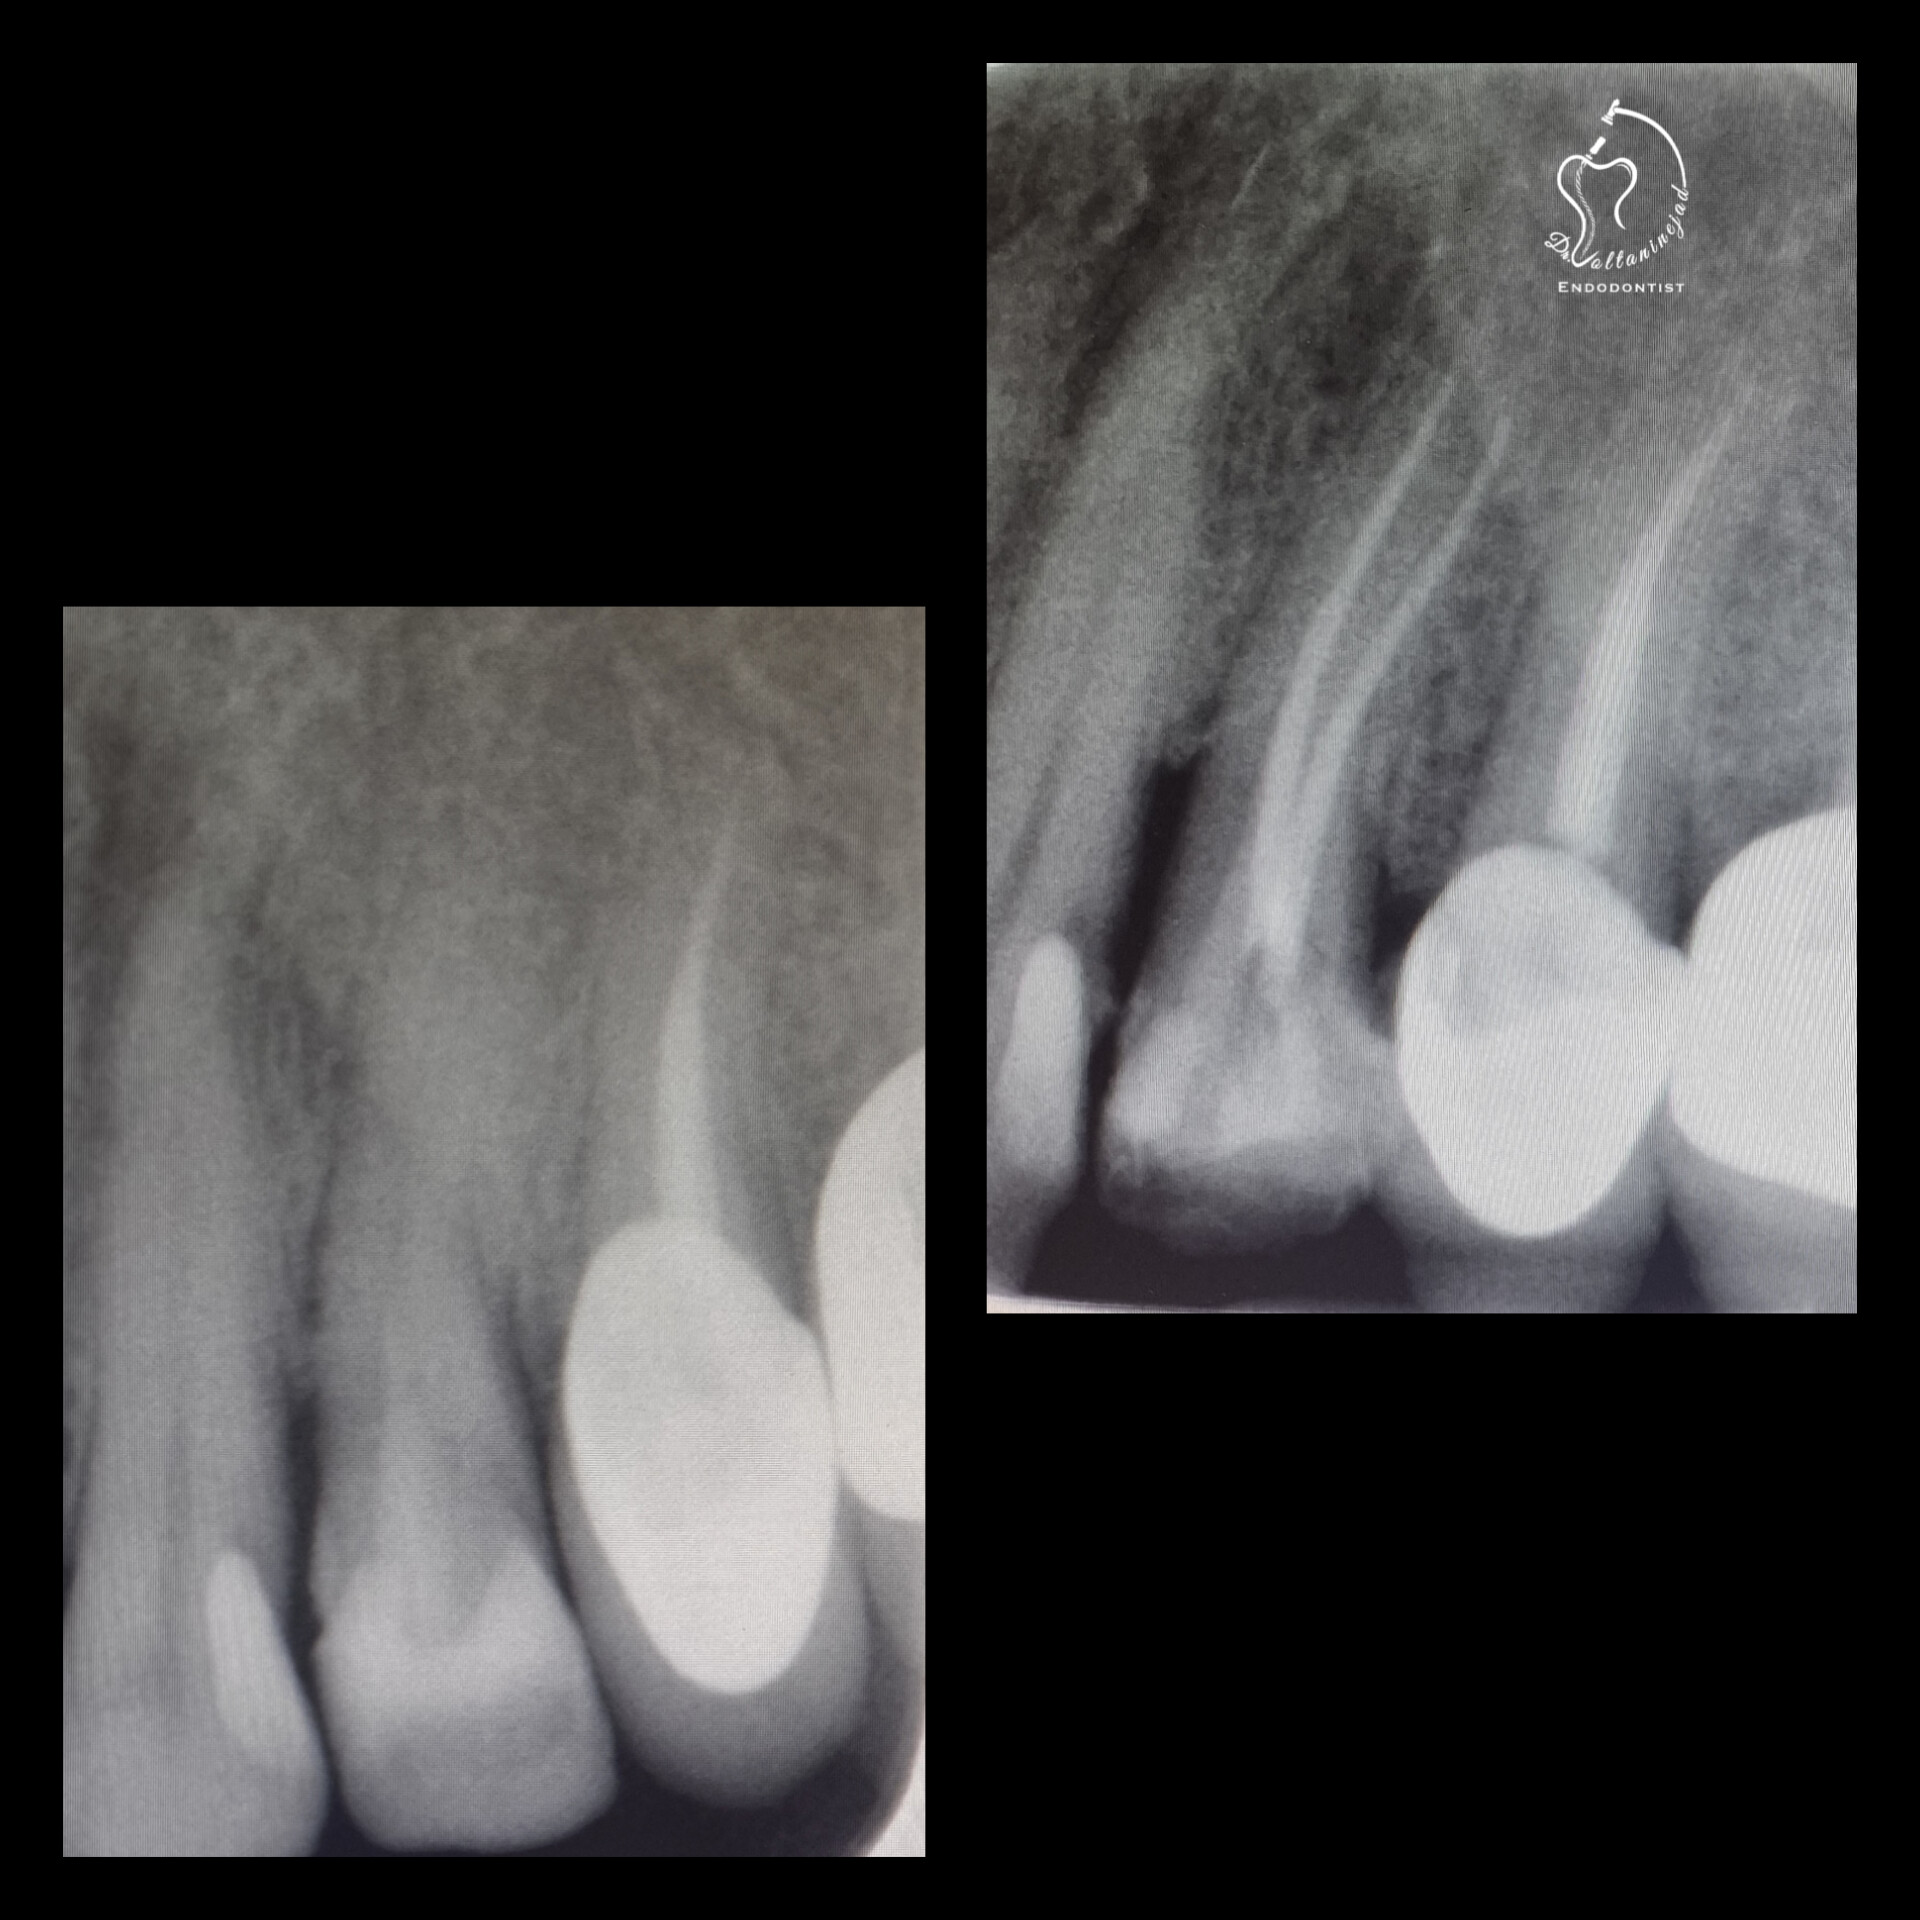

🔹 درمان ریشه دندان کانین با ضایعه وسیع

• شرح کوتاه: بیمار با درد و تورم شدید مراجعه کرد. پس از درمان ریشه تخصصی، ضایعه استخوانی طی ۶ ماه به‌طور کامل بهبود یافت.

• نتیجه: حفظ دندان و بازگشت عملکرد طبیعی.

درمان ریشه دندان کانین